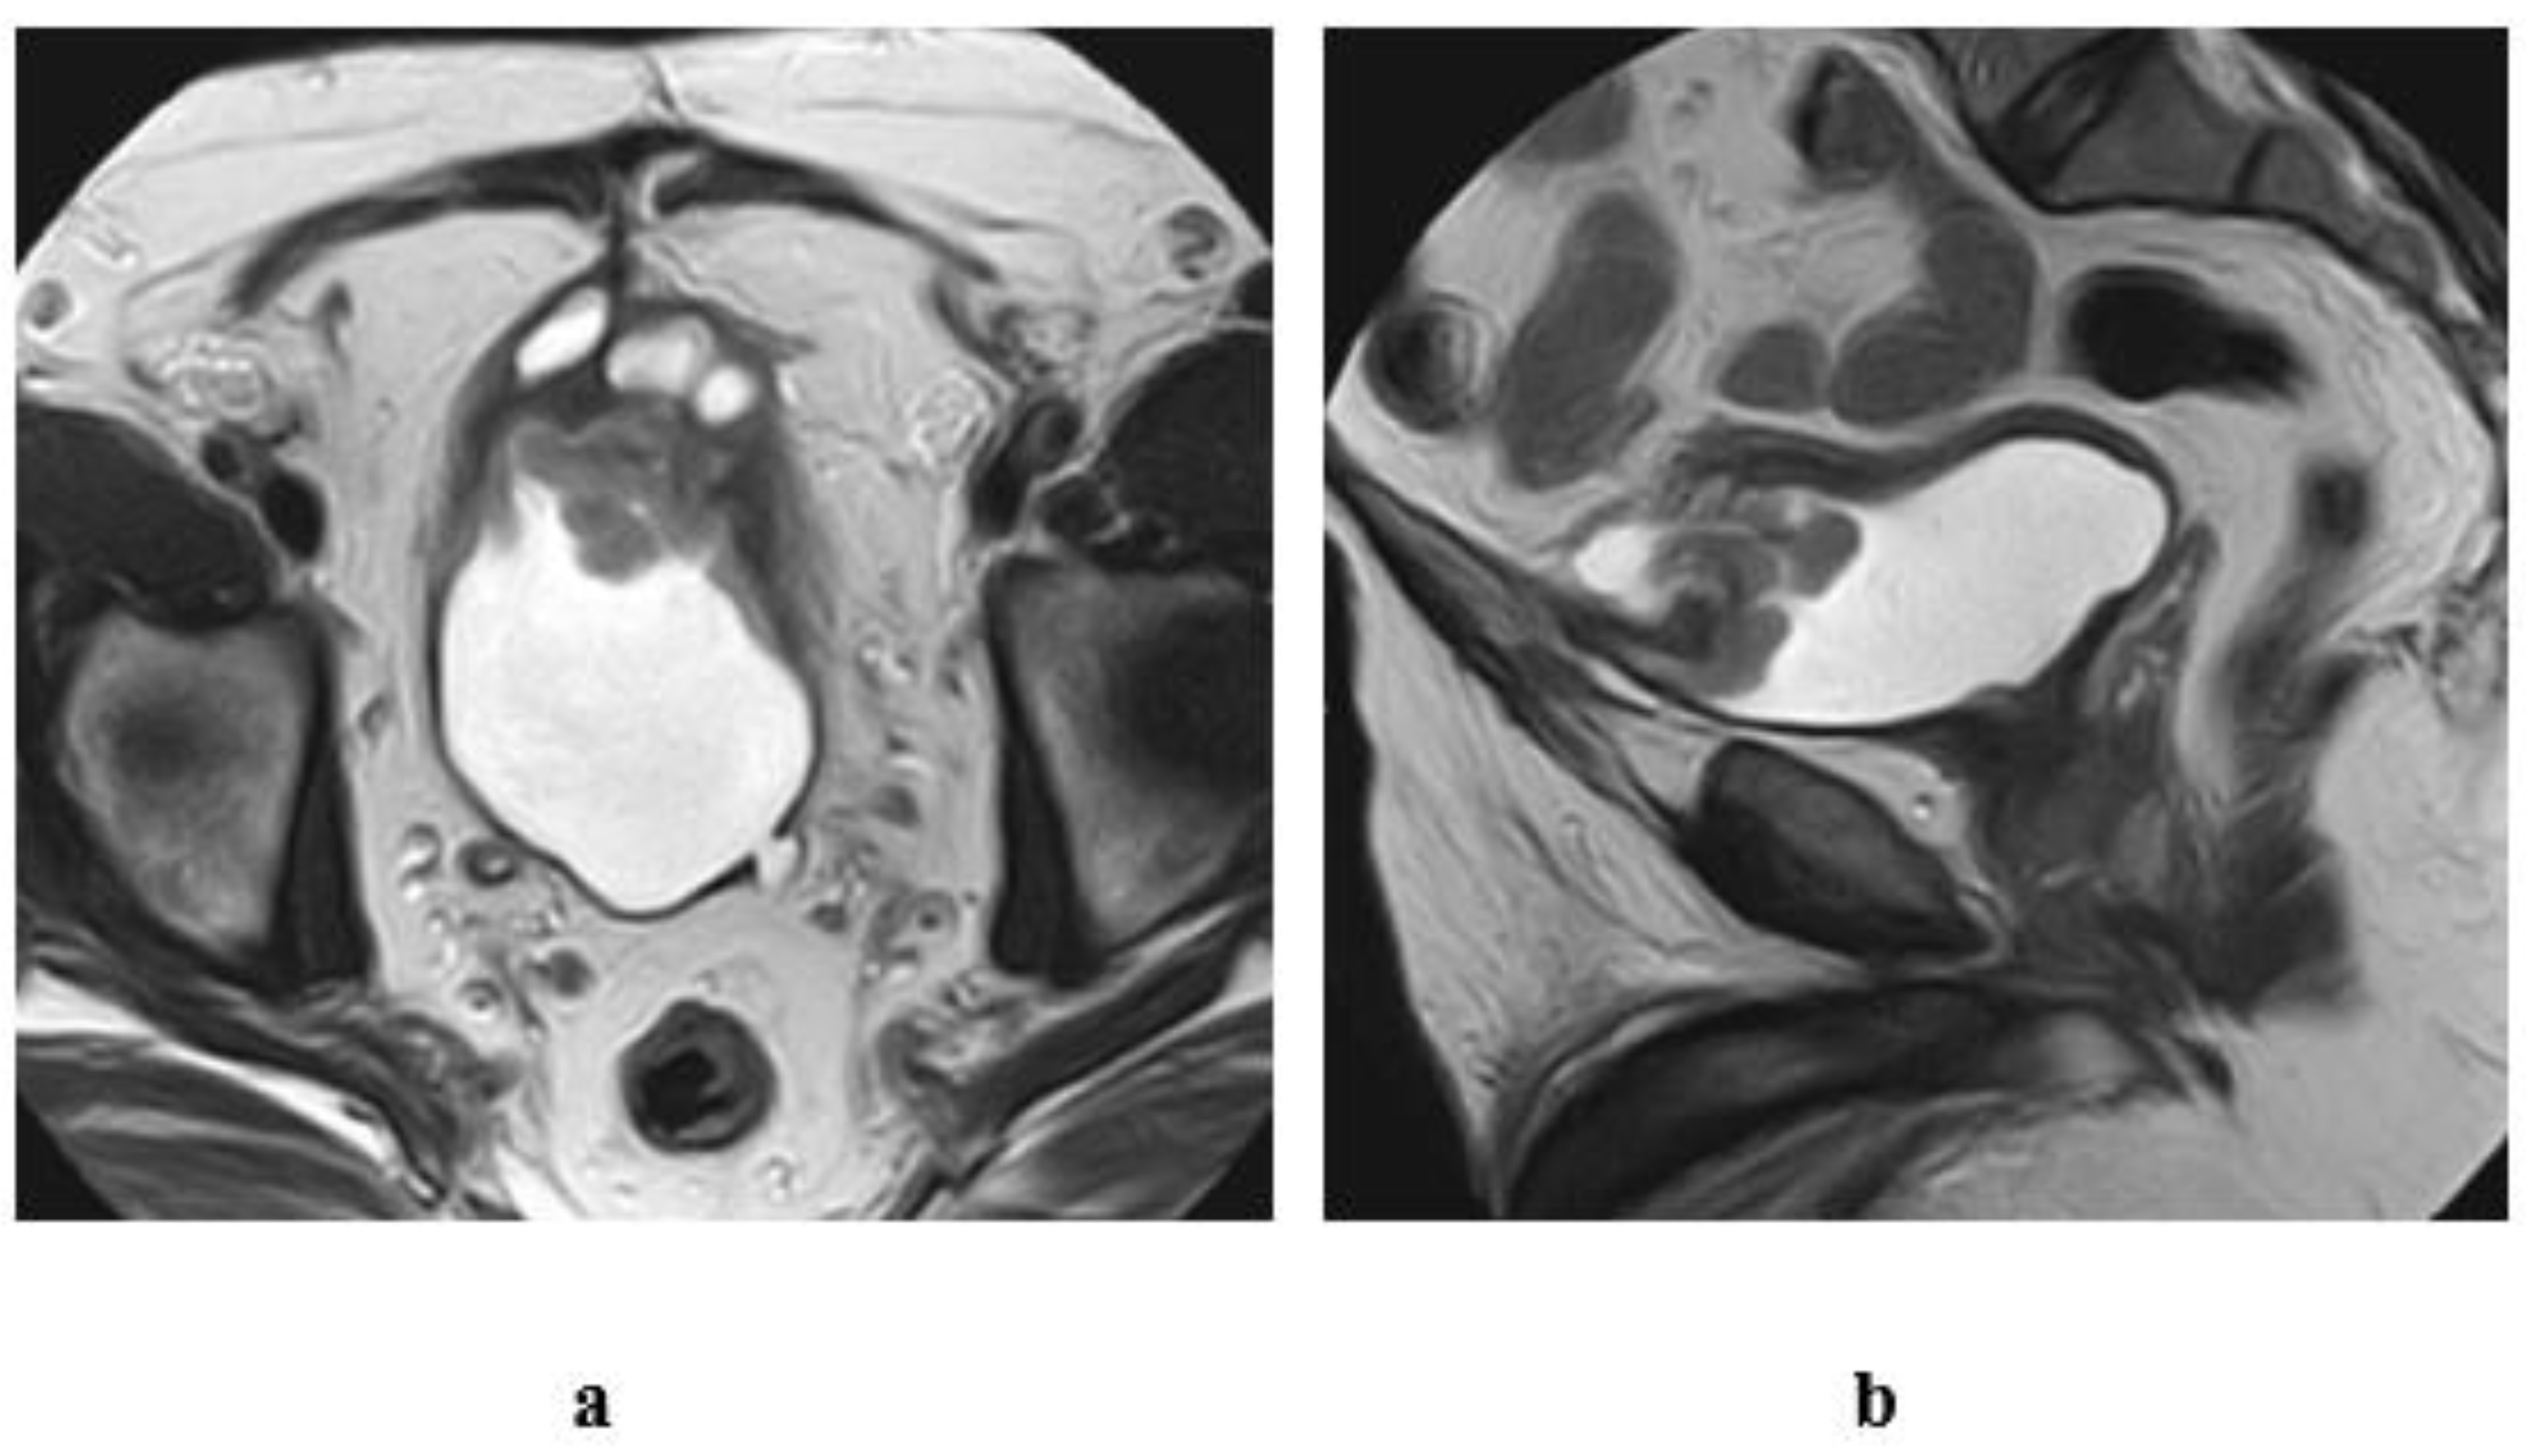

4. Intradiverticular Carcinoma

5. Ureterocele Urothelial Carcinoma